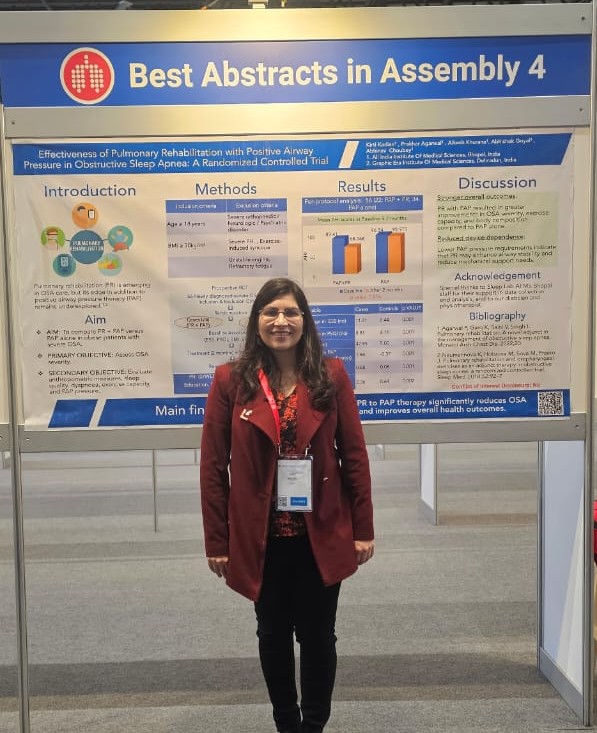

Dr Kirti Kadian

DM (AIIMS), MD

Pulmonary, Critical Care & Sleep Medicine

Interventional Pulmonologist, Intensivist & Sleep Expert

Ex. Senior Resident PGI Rohtak & AIIMS Bhopal

Best Research Paper Award AIIMS, 2024

Best abstract Award ERS Amsterdam, 2025

International Awards & Achievements

Event → European Respiratory Society Conference 2025

London Amsterdam, Europe

Dr. Kirti Kadian

Awarded Best Research Award